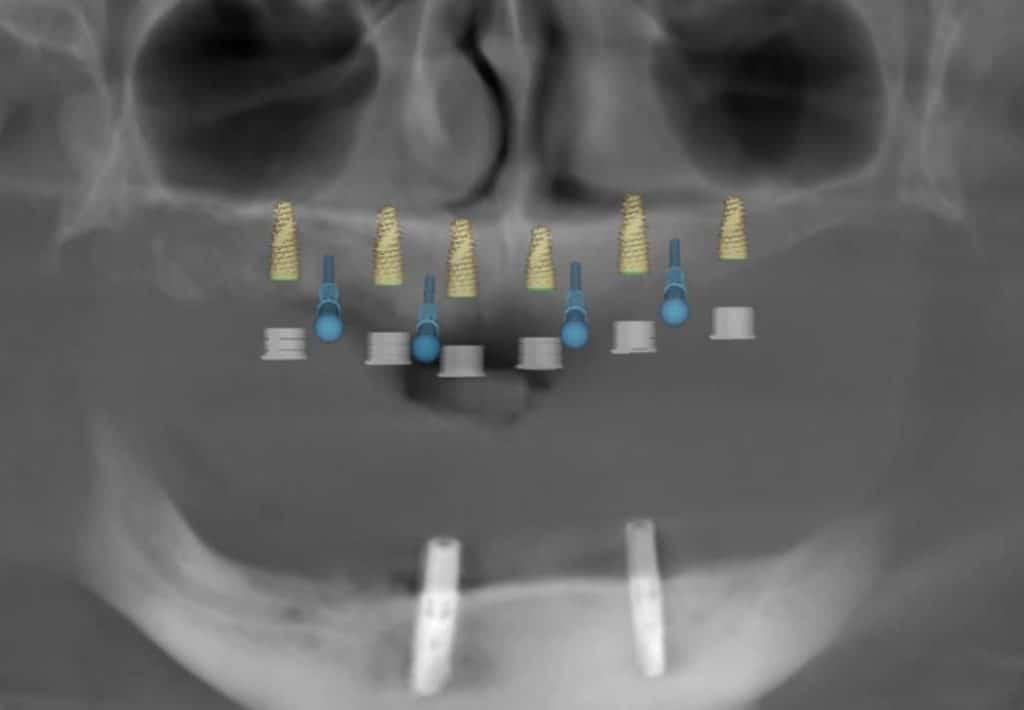

here a case where a full mouth réhabilitation was done by placing 6 implants

multiunit abutement were placed and a temporary bridge also was made for emergence profile shaping